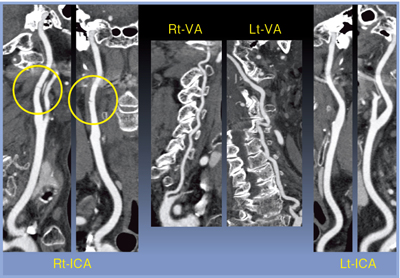

次に,頸部〜頭部CTAを施行し,3D再構成画像で,右内頸動脈の損傷が認められた。骨条件のMPR像では頸椎損傷はなく,内膜損傷のみであった(図5)。

脳血管への血流を確認する目的だけであれば,Volume ECのSD7で十分診断可能であり(図7),被ばく低減を行うことができた。

![]() 図6 症例2:CPR画像 |

![]() 図7 症例2:MIP画像 120kV,Volime EC:SD7,0.5s/rot,0.5mm×80,HP51, 再構成関数FC42 |